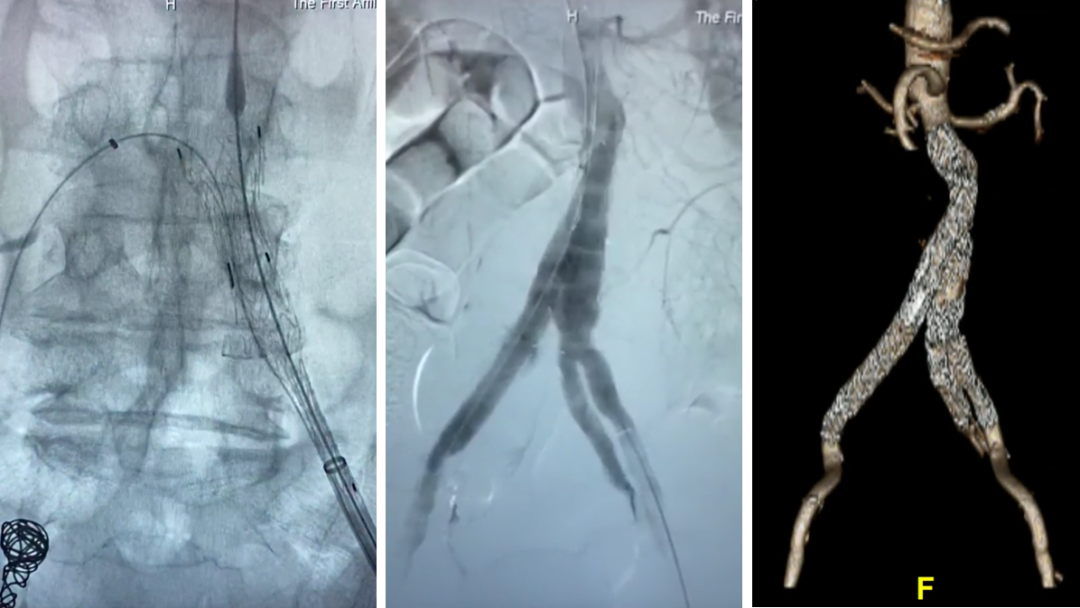

技术亮点:全球首款FDA批准的IBE ,双下肢入路 ,预置导丝通路 ,可重新定位(分段释放);low-profile设计(16Fr) ,65个月随访髂内通畅率98% ,I/III型内漏发生率为0。

适应证:髂总近端直径>17mm ,肾下至髂内开口长度>165mm ,适合复杂解剖(如76岁严重血管迂曲患者 ,联合开窗技术成功保留髂内)。

68岁男性 ,因腹主动脉瘤及双侧髂总动脉瘤入院。左侧采用商品化IBE支架、右侧行栓塞。术中利用牵引导丝快速超选髂内完成重建 ,右侧引入腹主主体 ,通过喇叭腿与IBE衔接 ,造影隔绝瘤腔 ,术后1月随访显示瘤体隔绝良好 ,左侧髂外分支通畅。

左侧IBE+右侧栓塞

利用牵张导丝,快速超选髂内,完成髂内重建

右侧引入腹主主体,喇叭腿与IBE桥接。造影隔绝

术后1月随访,整体隔绝,左侧髂内外分支通畅